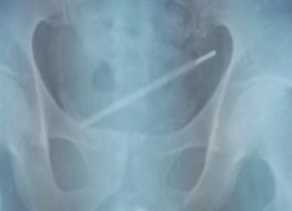

Pria ini Masukkan Termometer ke P*nis, Terjebak di Kandung Kemih 11 Hari

INHILKLIK.COM, CHINA - Seorang pria di China berakhir di rumah sakit setela.